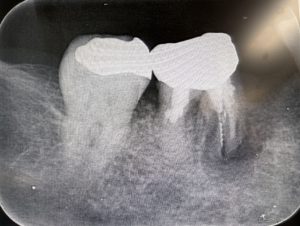

午後のオペ

右下5、6番の欠損に対してストローマンSPインプラントを植立しました。

大体毎回1本10分間ぐらいで終わります。 今回は2本で20分間です。